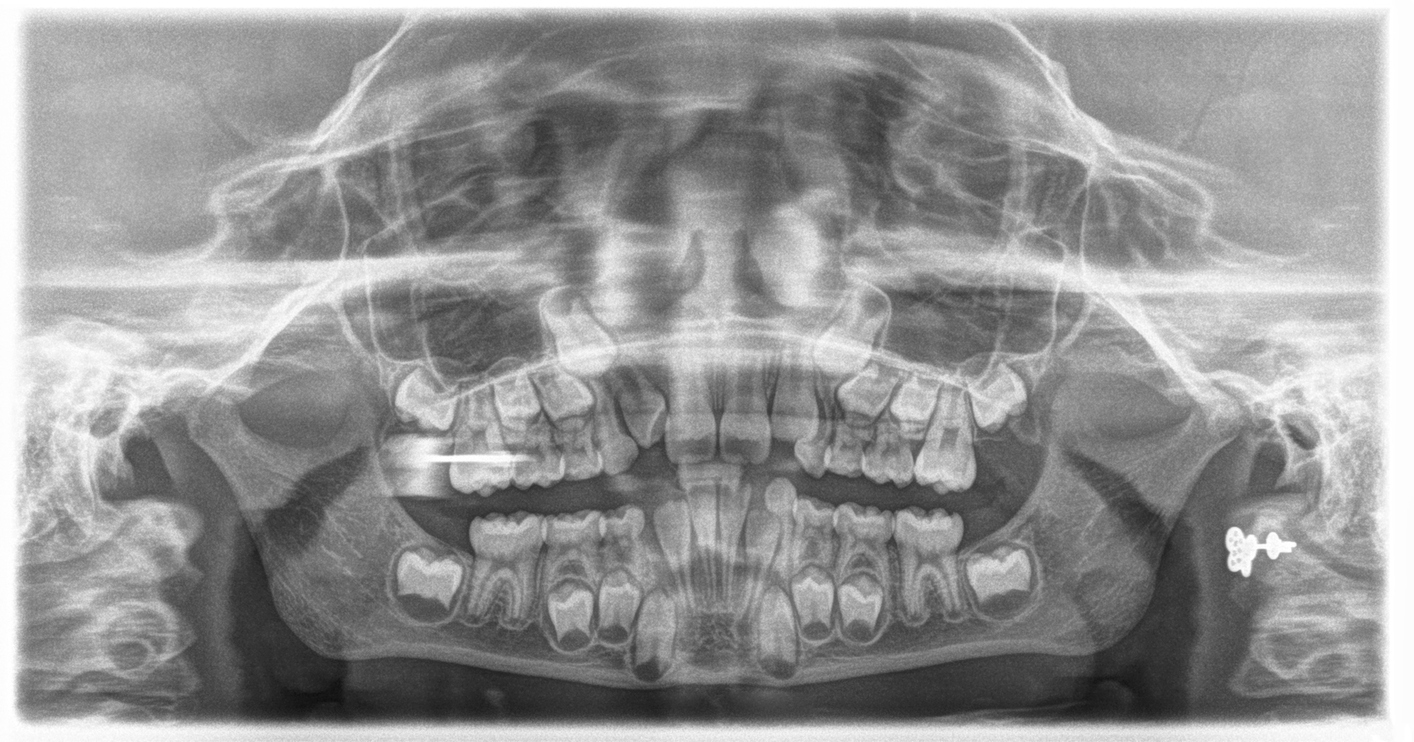

- Hiperdoncja rzekoma – nadliczbowe zęby są mniej rozwinięte i mogą występować w formie niepełnych zawiązków, które często są niewidoczne gołym okiem i odkrywane tylko w wyniku prześwietlenia rentgenowskiego.

Rozpoznanie hiperdoncji w większości przypadków jest możliwe tylko przy użyciu badań diagnostycznych, takich jak zdjęcia rentgenowskie. Zwykłe badanie stomatologiczne może nie ujawnić wszystkich dodatkowych zębów, szczególnie w przypadku, gdy są one w fazie wczesnego rozwoju. Z tego powodu, w przypadku podejrzenia hiperdoncji, konieczne może być wykonanie panoramicznego zdjęcia RTG jamy ustnej, które pozwala na dokładne zlokalizowanie nadliczbowych zębów.